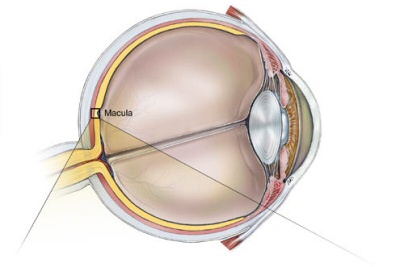

Göz küresinin arka duvarında bulunan retina tabakasının merkezine "Makula" ismi verilir. Makula bölgesinin düz bakıldığında cisimleri ayrıntılı ve net olarak görmede önemli bir işlevi bulunur. Bu bölgede bulunan fotoreseptör hücrelerinin ilerleyici kaybı ile oluşan bozulma Makula Dejenerasyonu olarak adlandırılır ve halk arasında "Sarı Nokta Hastalığı" olarak bilinir. İleri yaşlarda görme kaybının en önemli sebeplerindendir.Sarı nokta hastalığı için risk faktörleri nelerdir?

Normal Makula